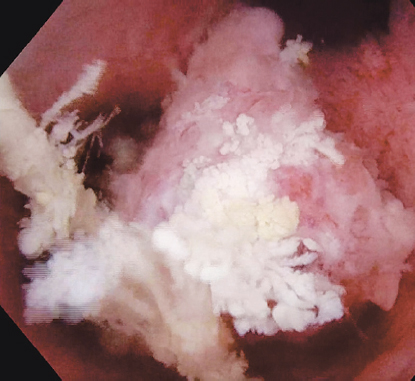

Принято решение о повторном оперативном лечении перкутанным доступом. В положении пациента на животе под эндотрахеальным наркозом выполнена пункция полостной системы правой почки через нижнюю группу чашек, пункционный тракт бужирован до 24 Ch и установлен кожух Амплатц. С помощью гибкого видеонефроскопа произведена ревизия полостной системы правой почки, в проекции зоны предыдущей резекции опухоли отмечается рубцово-измененная стенка лоханки, в области рубца рецидива новообразования не выявлено. При дальнейшей ревизии полостной системы правой почки в проекции верхних групп чашек выявлена крупная опухоль крупноворсинчатой структуры на широком основании (рис. 7). Выполнить ее резекцию не представлялось возможным из-за острого угла «атаки» и невозможности адекватно провести инструмент в верхнюю группу чашек. Принято решение о применении дополнительного перкутанного доступа в проекции верхних групп чашек. Под ультразвуковым и визуальным контролем прецизионно был произведен второй доступ в верхнюю группу чашек вблизи с новообразованием (рис. 8).

Рис. 7. Опухоль полостной системы правой почки, расположенная в проекции верхних групп чашек

Fig. 7. Tumor of the cavitary system of the right kidney located in the projection of the upper groups of calyces

Произведено бужирование пункционного хода до 28 Ch, в почечную лоханку заведен резектоскоп. Учитывая размер новообразования и его широкое основание было принято решение выполнить резекцию новообразования инструментом с биполярной подачей энергии (рис. 9).

Рис. 9. Этап резекции опухоли полостной системы почки с применением биполярного вида энергии

Fig. 9. Stage of resection of the tumor of the pelvicalyceal system of the kidney with a bipolar type of energy